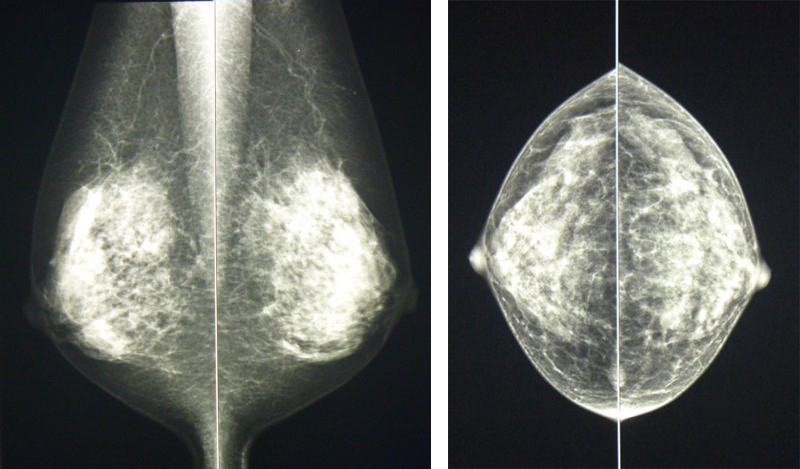

乳房のエックス線撮影のことを、マンモグラフィといいます。乳房は柔らかい組織でできているため、専用のエックス線撮影装置を使用します。 マンモグラフィは、乳がんをはじめ乳房にできる病気の多くを見つけることができます。特に、しこりとして触れない早期の乳がんのサインである石灰化を鮮明に写し出せるのが大きな特徴です。マンモグラフィは乳房の全体像を1枚に写し出すことができるため、左右を比較して診ることができます。また、過去の画像と比較して、組織の微妙な変化をとらえることができます。

マンモグラフィは、乳房を左右片方ずつ、撮影台と透明なプラスチックの板で挟んで乳腺を引き伸ばし、乳房を均等な厚さに圧迫して撮影します。そうすることにより、乳腺内部の様子を鮮明に写し出すことができ、さらに、被ばく線量を減らすというメリットもあります。圧迫の際に痛みを伴うことがありますが、肩の力を抜くと痛みが和らぎます。